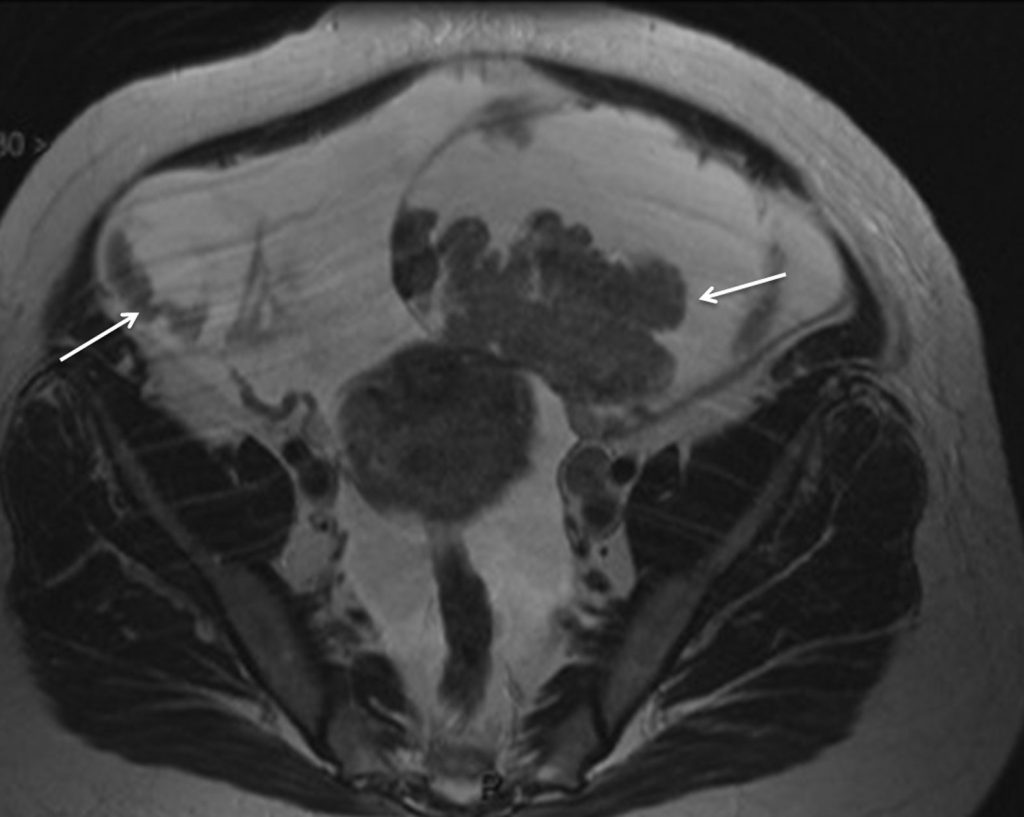

Fig. 23.5 Cystadénocarcinomes ovariens.

Coupe IRM en incidence axiale pondérée en T2 retrouvant une tumeur ovarienne bilatérale mixte avec une composante solide en signal intermédiaire en T2 et une volumineuse ascite.

Source : CERF, CNEBMN, 2022.